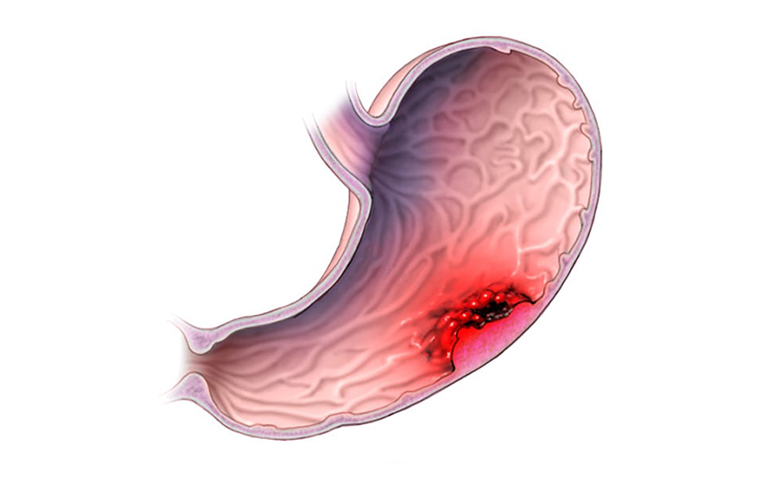

Mide Kanseri

Mide kanseri çeşitli nedenlerden dolayı mide mukozasında kötü huylu tümörlerin gelişmesi sonucunda gerçekleşir.